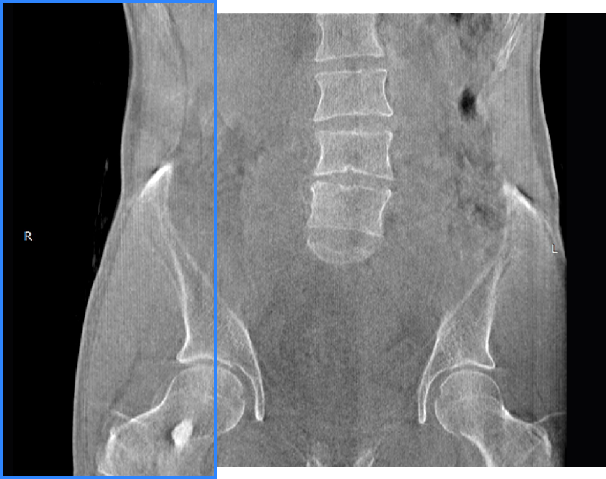

髖關(guān)節(jié)

精準(zhǔn)診斷

手術(shù)方案規(guī)劃

術(shù)后隨訪(fǎng)